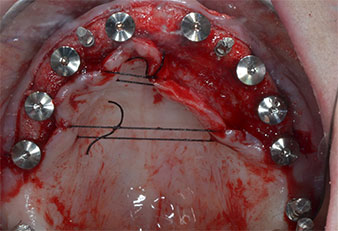

Tres años después, llegó el momento de colocar una prótesis del mismo tipo en el maxilar superior. Basándose en una planificación mediante tomografía computarizada de haz cónico (CBCT, por sus siglas en inglés), se evitó la necesidad de realizar una elevación del seno utilizando implantes cortos, mientras que una plantilla quirúrgica sirvió para transferir las posiciones planificadas al borde alveolar (figuras 1 y 2).

Debido al hueso relativamente duro (D2) existente en el sector anterior, los sitios de los implantes largos de 10 mm de las posiciones 11 y 21 se finalizaron con una fresa rotatoria de 4 mm de diámetro, en combinación con un contra-ángulo quirúrgico WS-75 L de W&H, el motor de implantes Implantmed de W&H y el módulo opcional Osstell ISQ de W&H. En cambio, debido a la existencia de hueso blando, los sitios posteriores se prepararon hasta un diámetro final de 3 mm utilizando el inserto Piezomed I3P. Por último, los implantes se colocaron a nivel crestal para su osteointegración durante tres meses (figuras 6-10). La prótesis existente se mantuvo sobre cuatro implantes provisionales (figura 8).